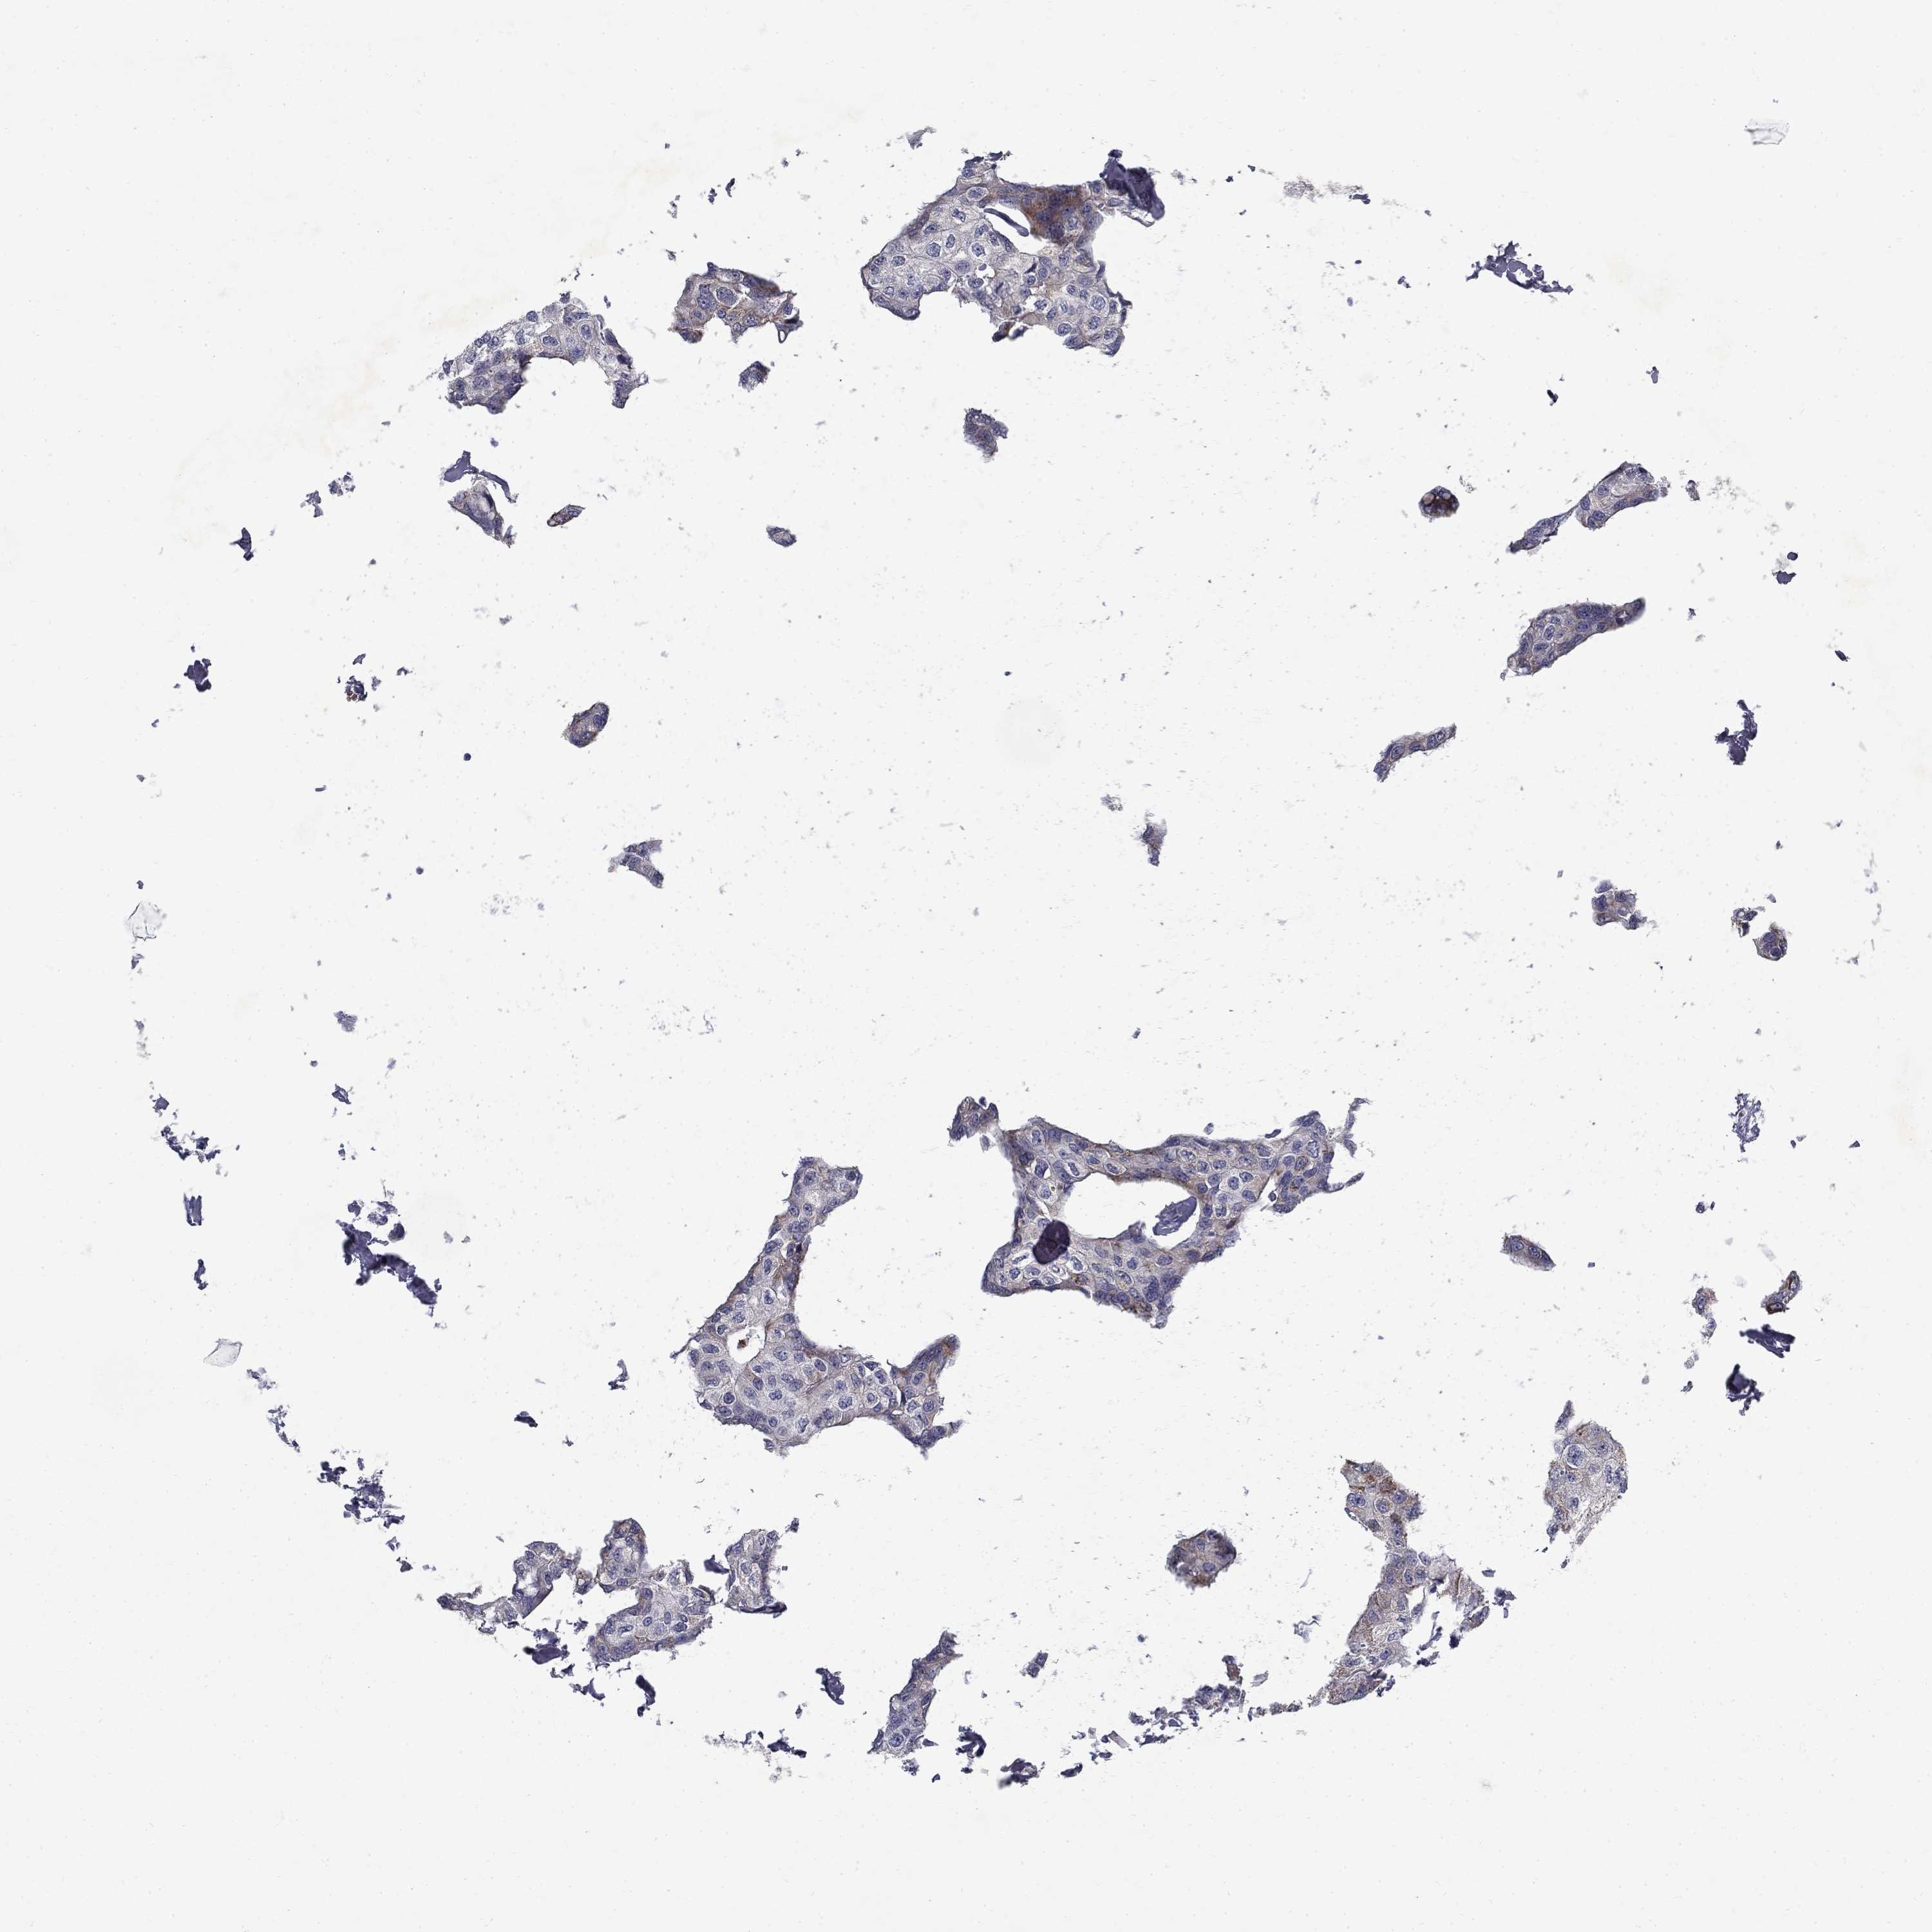

BRCA TCGA BRCA VALIDATION PROTEIN EXPRESSION